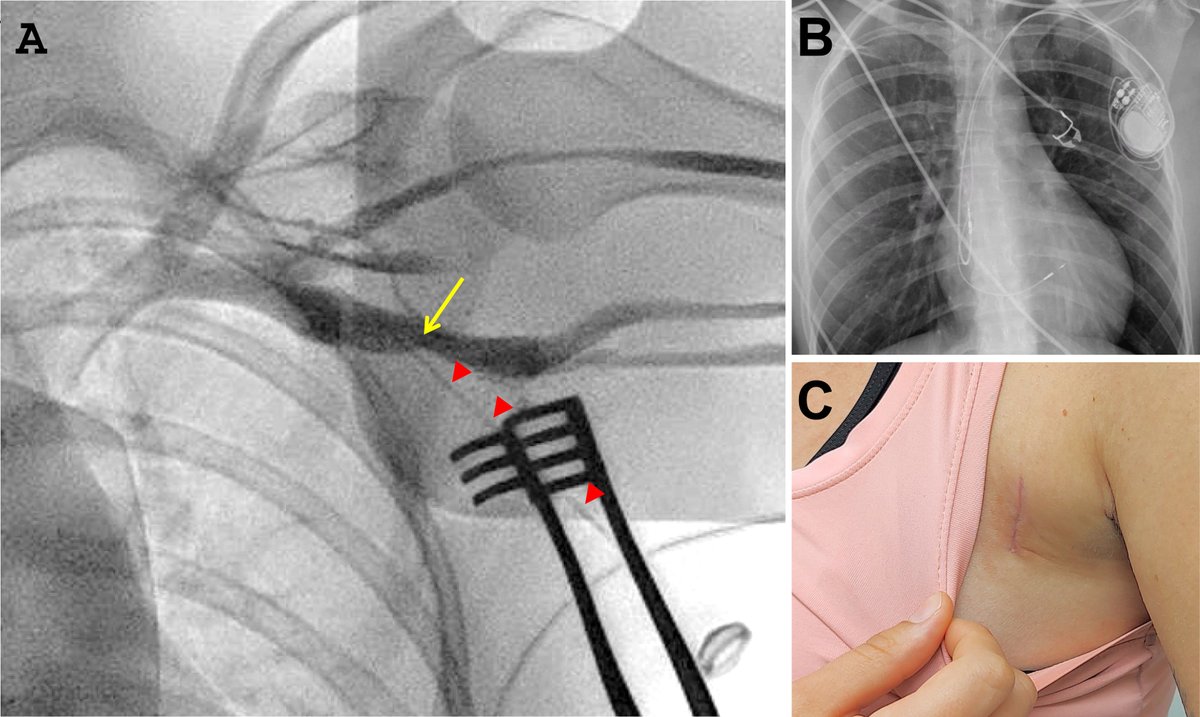

And the debate continues PhysioSync trial ⬇️⬇️⬇️ CSP is inferior to BiVP for CRT in HFrEF and LBBB (QRSD ≥ 130 msec) including HF events, LVEF improvement and death #EPeeps #ESCCongress